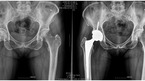

평소 사람들과 어울리기를 좋아해 자연스레 술자리도 잦은 평범한 직장인 강모(47세, 남)씨. 6개월 전부터 왼쪽 사타구니와 엉덩이 쪽으로 통증이 있었다고 한다. 시간이 지나면 낫겠지 하고 기다리다가 통증이 심해져서 찾아간 병원에서 뜻밖에 고관절 무혈성 괴사증이라는 진단을 받았다. 가정주부 권모(54세, 여)씨는 어릴 적부터 왼쪽 다리가 약간 짧고...